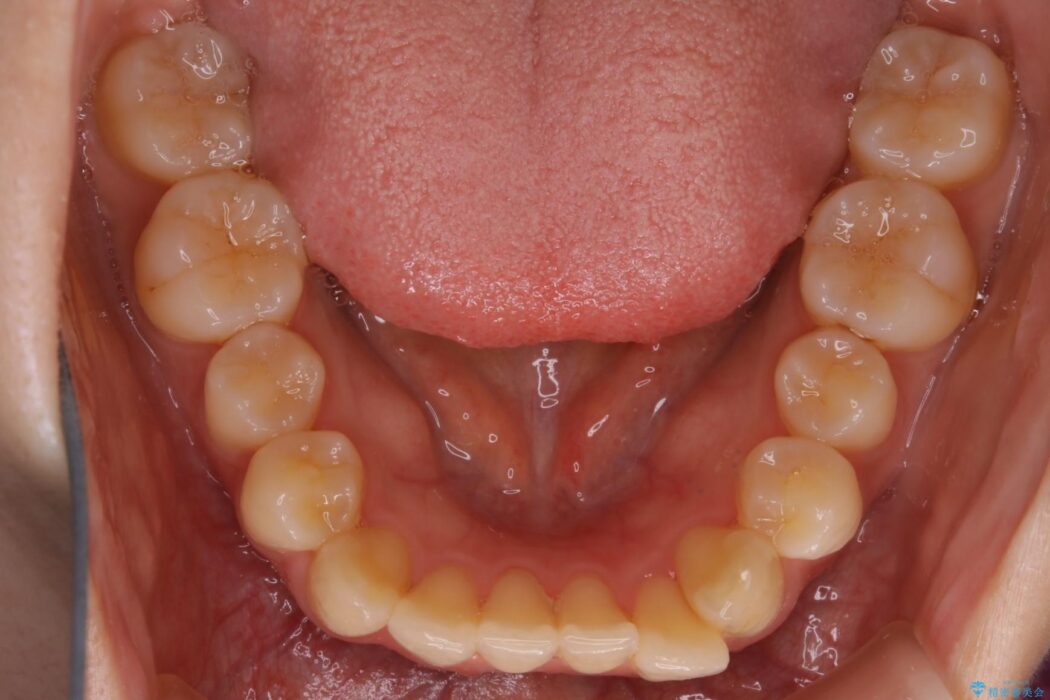

下額前歯が少しガタついていることを気にされて来院されました。

検査をしたところ奥歯の噛み合わせなどに問題が見られなかったため、軽度のねじれがある下顎前歯に焦点を当てた部分矯正の適応が可能と判断し、インビザラインのライトパッケージをご提案しました。

本症例では奥歯に関して問題がほぼ見られなかったため、部分矯正を行うことが可能と判断しました。

通常の全体矯正と比べピンポイントの部分矯正となると、動かす歯が少なくなるため治療期間が格段に短くなり、費用が抑えられることがメリットとして挙げられます。